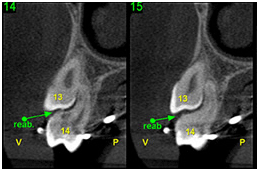

• Avaliar o grau de reabsorção radicular de dentes adjacentes a caninos retidos

Reabsorção radicular adjacente a dentes retidos Reabsorção radicular adjacente a dentes retidos